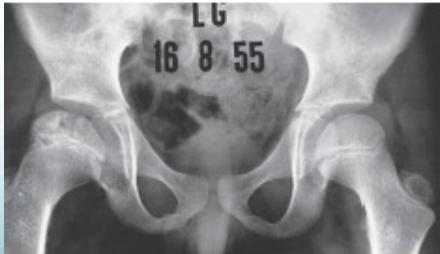

Radiographic Stages:

-

Initial/ Bone Death Stage - May initially appear normal on x-ray

- Increased density followed by collapse

Revascularization and Repair Stage - Reduced density and fragmentation on x-ray

Distortion and Remodeling Stage - Distortion, flattening (coxa plana)

- Enlargement (coxa magna) with partial uncoverage

Radiological Progression:

Progression: Sclerosis → Collapse → Fragmentation → Remodeling

Imaging Examples: